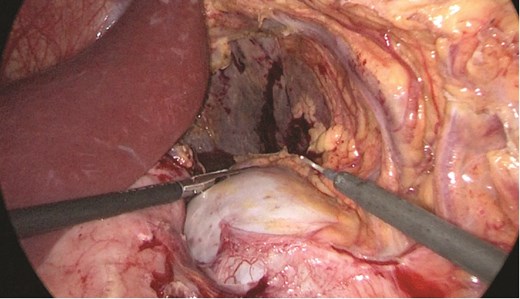

Multidisciplinary discussion was held to evaluate the most appropriate course of action for the patent condition, and the consensus was reached to pursue embolization as a first intervention. Embolization was performed by interventional radiology with no complications post-procedure, and the patient was optimized prior to her procedure. Patient was taken to the operating room in stable conditions. The spleen was enlarged around 20 cm. Inferiorly, the omentum and part of the transverse colon was attached to the spleen (Fig. 3), so we freed the omentum from the splenic tissue. The dissection continued until reaching short gastric vessels and entering the lesser sac (Fig. 4). Once the lesser sac was entered, the splenic vessels were identified (Figs 5 and 6), the splenic vein was hugely dilated with multiple collateral branching vessels at the hilum. Gaining posterior mobilization of the vein was challenging. The splenic artery was tortuous from the insertion around itself (Fig. 7). After complete mobilization of the fundus, we elected to divide each vessel starting with the splenic artery so we can achieve full mobilization of the vein (Fig. 9). After controlling the splenic artery, the splenic vein was dissected proximal to the splenic hilum (Fig. 8). It was hugely dilated and its wall is thickened secondary to AV fistula. It was difficult to achieve circumferential dissection, so we decided at that moment to convert to laparotomy to complete ligating the vein and to retrieve the specimen (Fig. 10a and b).

Anterior portion of the splenic vein seen posterior to the stomach.